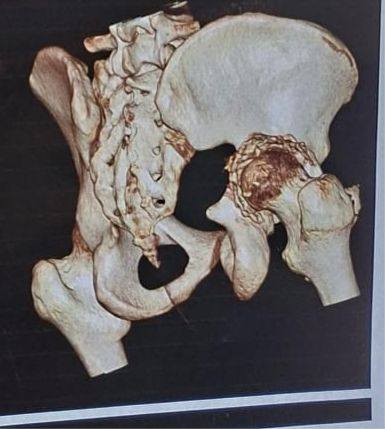

أ.د/ حسام الدين جاد – رئيس قسم جراحة العظام نجحت وحدة جراحات الحوض المتقدمة بقسم جراحة العظام والكسور في إجراء عملية معقدة لرد وتثبيت كسر مهمل بالجدار الخلفى للحق الحرقفى مع وجود خلع مهمل بالمفصل وتحرير العصب الوركى حيث انه حضر إلينا المريض يعانى من آلام فى الحوض وسقوط جزئى بالقدم بعد مرور شهرين من إصابته فى حادث وتم عمل اشعة فتبين وجود خلع مهمل مع كسر بالجدار الخلفى للحق الحرقفى بمفصل الفخذ وتم دخول الحالة للعمليات حيث تم استكشاف وتحرير العصب الوركى وعمل رد مفتوح للخلع وازالة التعظم بالانسجة المحيطة واعادة بناء الجدار الخلفى للحق باستخدام رقعة عظمية من داخل عظام الحوض وتثبيت الكسر بواسطة شرائح ومسامير وتم خروج المريض من العمليات بنجاح.